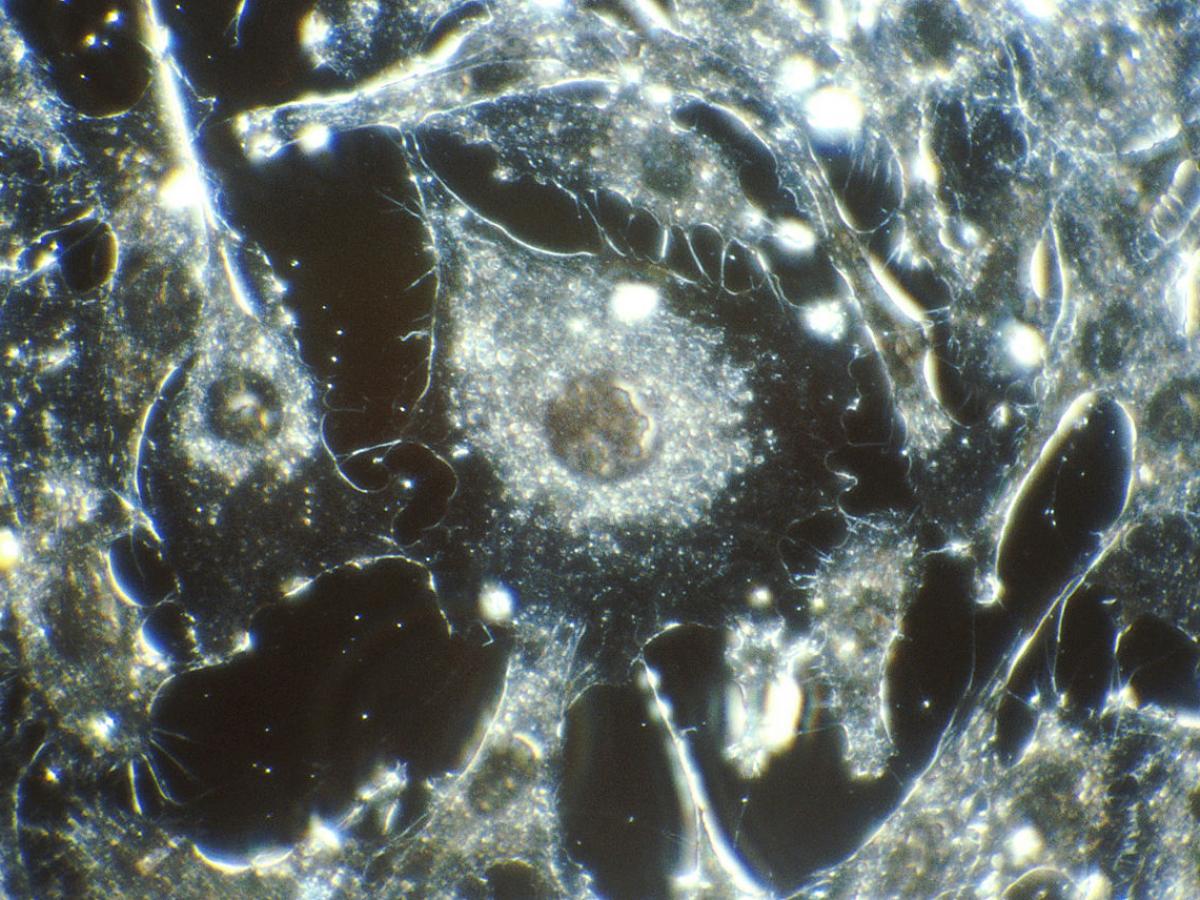

Врач-эндоскопист Натия Чехоева подчеркнула важность эндоскопических исследований в диагностике онкологических заболеваний желудочно-кишечного тракта, сообщает издание "Газета.ру".

Современные методы эндоскопии позволяют определить предраковые состояния на самых ранних стадиях, когда эффективность лечения максимальна. Если заболевания выявлены на первой стадии, вероятность полного выздоровления достигает 95% благодаря органосохраняющим операциям.